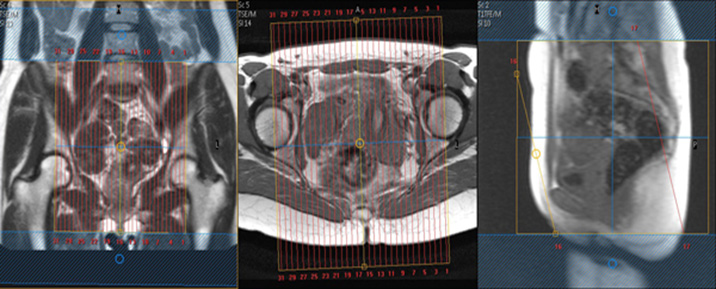

MR Female Pelvis UAE W/WO BODY Protocol

| Cor | T2 | SSFSE BH | 5mm | 1mm | No | Top pf kidneys to pelvis. | Scan sacrum to anterior abdominal wall. CONFIRM GOOD COIL PLACEMENT. Large FOV to include kidneys. Pelvic pathology is often related to renal pathology. |

| Axial | T1 | TSE | 5mm | 1mm | No | 20-24mm. Fit to patient. | Scan iliac crest to perineum. Freq A-P to avoid bowel motion ghosting into uterus and bladder. If there is a pelvic mass, please scan to include the whole mass. |

| Axial | T2 | TSE | 5mm | 1mm | No | 20-24mm. Fit to patient. | Scan iliac crest to perineum. Same parameters as AX T1 TSE. Freq A-P to avoid bowel motion ghosting into uterus and bladder. |

| Sag | T2 | TSE | 5mm | 1mm | No | 24mm. Fit to patient. | Scan mid-femoral head to mid-femoral head. Freq A-P. Consider using an anterior Sat band if lots of abdominal wall motion. |